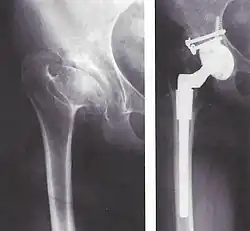

Die Behandlung gestaltet sich zumeist langwierig und ist individuell auf den Patienten und die Ausprägung der Erkrankung abzustimmen. Schuherhöhungen, Orthesen und Prothesen können bei milden Ausprägungen genügen. In vielen Fällen sind abhängig vom Status des Femurkopfes und der Ausprägung der Kniebeteiligung auch Eingriffe zur Korrektur der Hüfte und Stabilisierung des Knies zu erwägen. Weiterhin kann eine Verlängerung des Femurs und/oder der Tibia in Betracht gezogen werden, wobei hier die seit den 1950er Jahren angewandte, von Gawriil Abramowitsch Ilisarow etablierte Methode des Ring-Fixateurs oder der vollimplantierbare intramedulläre Marknagel als Behandlungsmethoden zur Verfügung stehen. Letzterer wurde Anfang der 1990er Jahre von Rainer Baumgart und Augustin Betz entwickelt und seitdem vielfach erfolgreich in der Beinverlängerung eingesetzt.

Bei der sog. Hirtenstabdeformität kann dem herangewachsenen Patienten auch eine Endoprothese implantiert werden.[7] Aufgrund der Seltenheit der Erkrankung und der Aufwendigkeit der Behandlung sollte diese in einem spezialisierten Zentrum erfolgen.